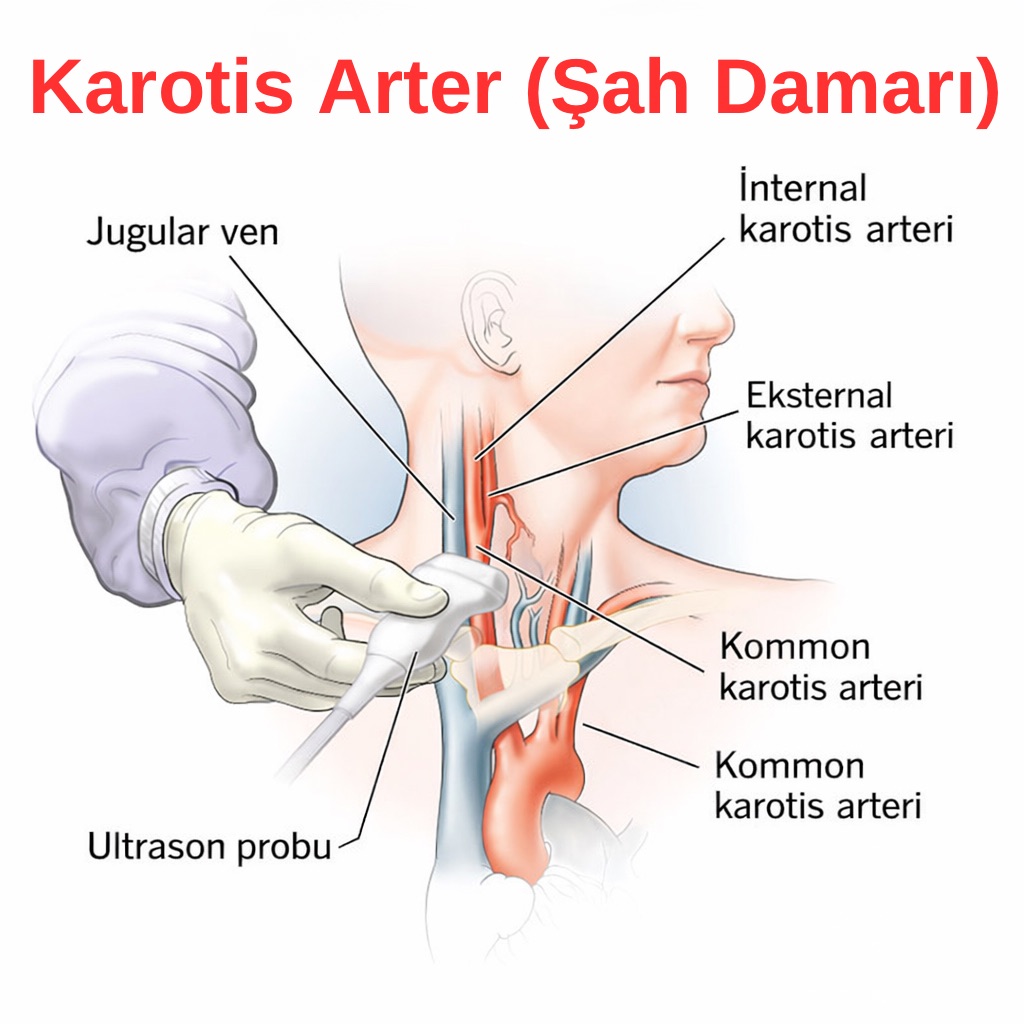

Karotis Ultrasonografi

Kliniğimizde yapılan karotis ultrasonografi, boyun damarlarında erken damar sertliği bulgularını saptamak amacıyla uygulanan, tarama odaklı bir değerlendirmedir. Bu inceleme, damar sağlığı hakkında fikir vermeyi ve kardiyovasküler riskin erken dönemde belirlenmesini hedefler.

🩺 1. İntima–Media Kalınlığı (İMK)

- Damar duvarının kalınlığı değerlendirilir.

- Erken ateroskleroz (damar sertliği) bulguları araştırılır.

- Kardiyovasküler riskin dolaylı göstergesi olarak kullanılır.

🩺 2. Plak Varlığı

- Şah damarlarında plak olup olmadığı kontrol edilir.

- Mevcut plakların yerleşimi belirlenir.

- Genel görünümü ve yaygınlığı incelenir.

🩺 3. Damar Lümeni Hakkında Genel Değerlendirme

- Belirgin bir daralma şüphesi olup olmadığına bakılır.

- Kan akımının serbest olup olmadığına dair genel gözlem yapılır.